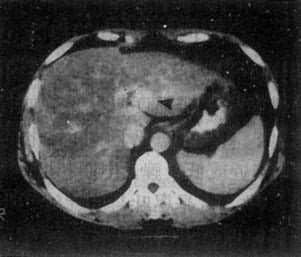

1.原发性肝癌 CT平扫绝大多数是低密度病灶,少数可以是低密度、等密度与高密度混合的病灶。肿瘤可以是单个或多个结节,也可呈巨块状。较大肿瘤因出血坏死和囊变而致密度不均匀,中心部常出现更低密度区,其边缘部呈结节状。肿瘤边界多不清,少数边界清楚并有包膜。增强扫描肝癌区略有增强或不增强,而正常肝增强,因而使肿瘤境界更为清楚。癌变区可出现密度稍高的结节或隔,但其增强程度多不如正常肝。动态扫描时,即快速静脉注射造影剂并于开始注射后15~25秒内即行扫描,由于肝癌由肝动脉供血且供血丰富而迅速,而造影剂尚未到达肝内门静脉形成实质期,故肝癌结节可成为高密度,甚或显出高密度的异常肿瘤血管。但肝癌增强的时间较短暂,2~3分钟内即恢复为原来的低密度状态(图4-3-5)

CT增强扫描,肝右叶有一较大圆形低密度肿块(↓),其边缘

部可见多个较密度的强化结节,其强化程度不如正常肝,中

心部仍为未强化的低密度区

除了上述密度改变外,CT还可能看到另外一些改变,包括①癌瘤处体积增大,轮廓隆凸;②肿瘤压迫肝门和(或)肝裂,使之变形和移位;③门静脉内瘤栓,表现为门静脉增粗,密度不均,增强后可见腔内充盈缺损影或门静脉不增强;④邻近器官如胃、胰、肾的受压移位;⑤附近或远处淋巴结增大(转移),腹水或其他脏器转移。